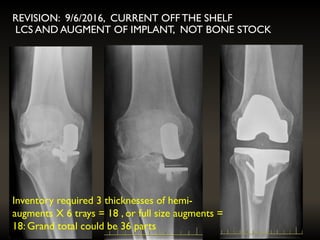

REVISION: 9/6/2016, CURRENT OFF THE SHELF

LCS AND AUGMENT OF IMPLANT, NOT BONE STOCK

Inventory required 3thicknesses of hemi- augments X 6 trays = 18 , or full size augments = 18: Grand total could be 36 parts REVISION: 9/6/2016, CURRENT OFF THE SHELF LCS AND AUGMENT OF IMPLANT, NOT BONE STOCK

PRE-OP PLANNING ANDCT SCANNING • Tray size would be known • Augment thickness planned and manufactured • Bearing thickness still not predictable • Saving on inventory required

Inventory required 3 thicknesses of hemi-

augments X 6 trays = 18 , or full size augments =

18: Grand total could be 36 parts

3YRS POST OPLEFT KNEE